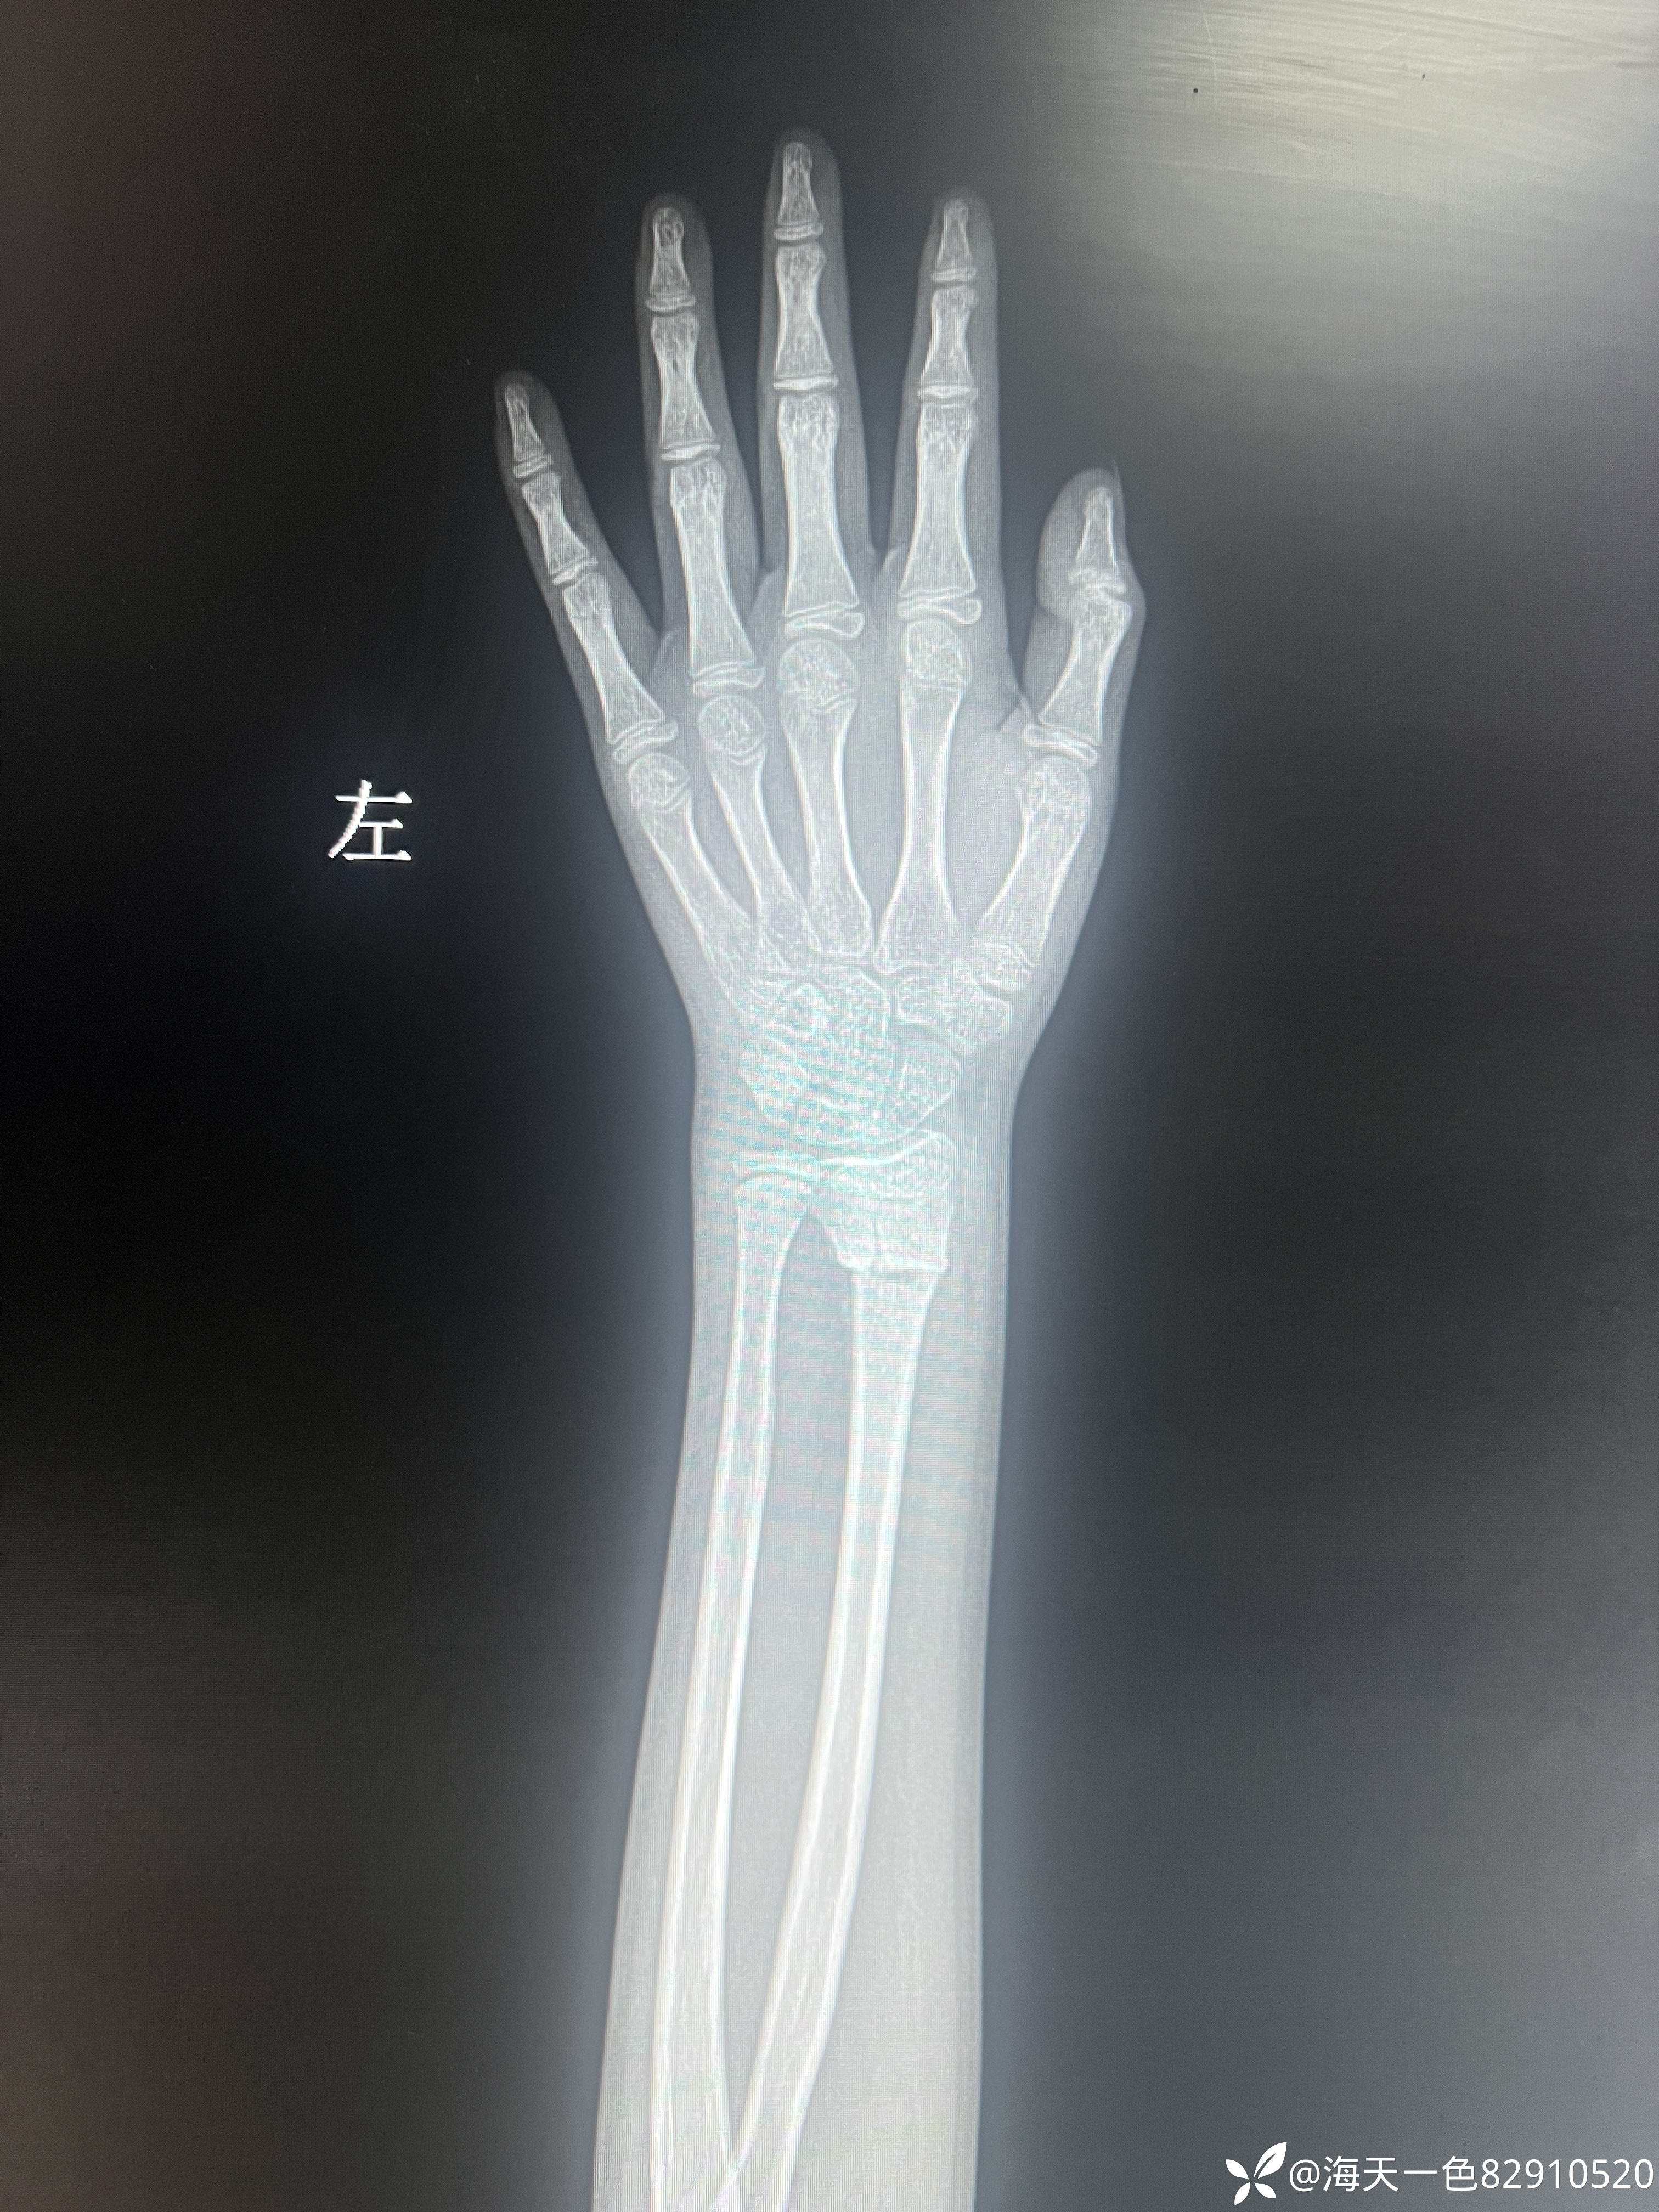

桡骨远端骨折

【患者信息】:患儿男性,14岁,

【主诉】:跑跳时不慎摔伤左腕关节肿痛14天

【临床诊断】:左桡骨远端骨折

【治疗经过及结果】:建议手术手术治疗,患儿家属未手术治疗,外院进行手法复位,复位拍片如下